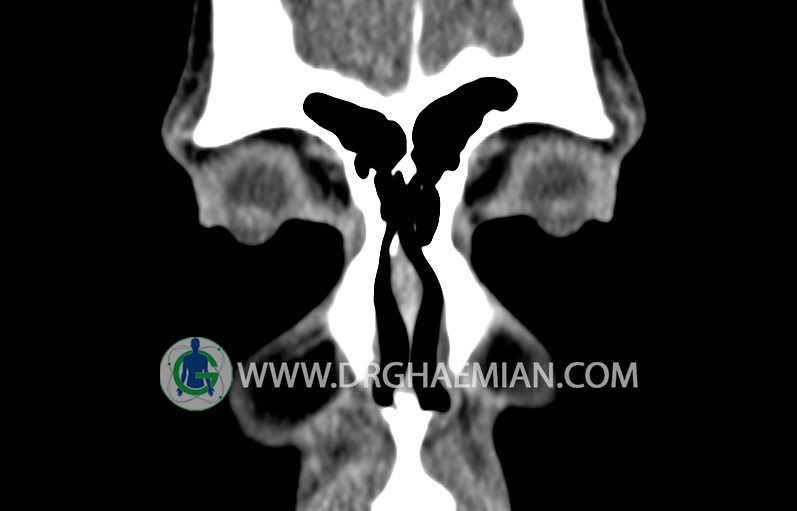

در HRCT اسپيرال از سينوس هاي پارانازال مقاطع کرونال و آگزيال ( 16 اسلايس و مقاطع ظريف 1.5 mm بدون فاصله ، با پنجره استخواني و نسج نرم ) :

– انحراف سپتوم مياني بينی به راست